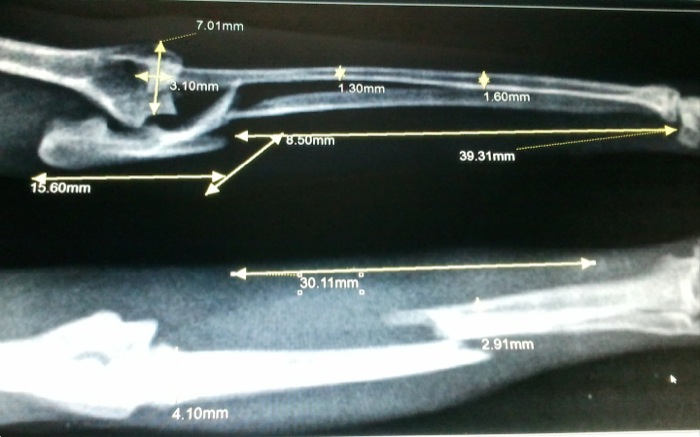

| Pruebas | Radiografía que muestra fractura múltiple de cúbito izquierdo que abarca la zona articular y separación del radio ( fractura de Monteggia). En la derecha hay una fractura de radio y cúbito diafisaria media. |

La fractura diafisaria media de radio del miembro derecho no presenta complicación aparente pero la lesión del miembro izquierdo con la fractura de Monteggia (fractura de cúbito con dislocación de cabeza de radio) no es sólo una lesión ósea.

El detalle de esta lesión nos plantea un reto. Estamos frente a una fractura compleja en huesos finos y fisurados y a nivel articular con luxación. Lo tiene todo para una cuidadosa resolución. Hay buena sensibilidad a nivel distal así que entramos en quirófano.